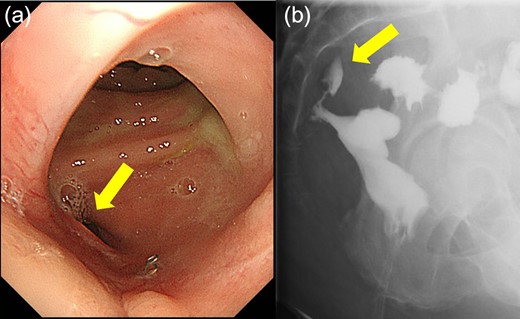

Case 1 was a 71-year-old man with a BMI of 29.7 kg/m2. Laparoscopic low anterior resection (LAR) and ileostomy was performed for rectal cancer in 2017 years. Postoperative fever and lower abdominal pain were noted, and colonoscopy was performed, and anastomotic leakage was noted with a correction of about 1/2 around the 6 o’clock direction of the anastomotic region, and fistula and formation of a large abscess cavity. After identification (Fig. 1), a tube was inserted for drainage and conservative treatment was performed. The patient was discharged on POD 46. Four months after the operation, marked improvement in the abscess cavity was noted but still remained (Fig. 2a and b). Anastomotic leakage was almost improved by colonoscopy at 17 months after surgery, but at the preference of the patient we performed colostomy 22 months after surgery (Fig. 3). It took a long time to improve intestinal movement of the colon because the large intestinal tract had not been used for a long time, and conservative treatment was performed using a nasogastric tube for paralytic ileus. Diet was initiated 7 days after surgery, and the patient was discharged from the hospital 14 days after surgery. The Wexner score [2] was 19 points one month after closure, 17 points 3 months after the operation and 16 points after 6 months after the operation, and severe anal dysfunction was observed, but gradually improved.

Colonoscopy shows that the suture failure has improved with only a slight depression.